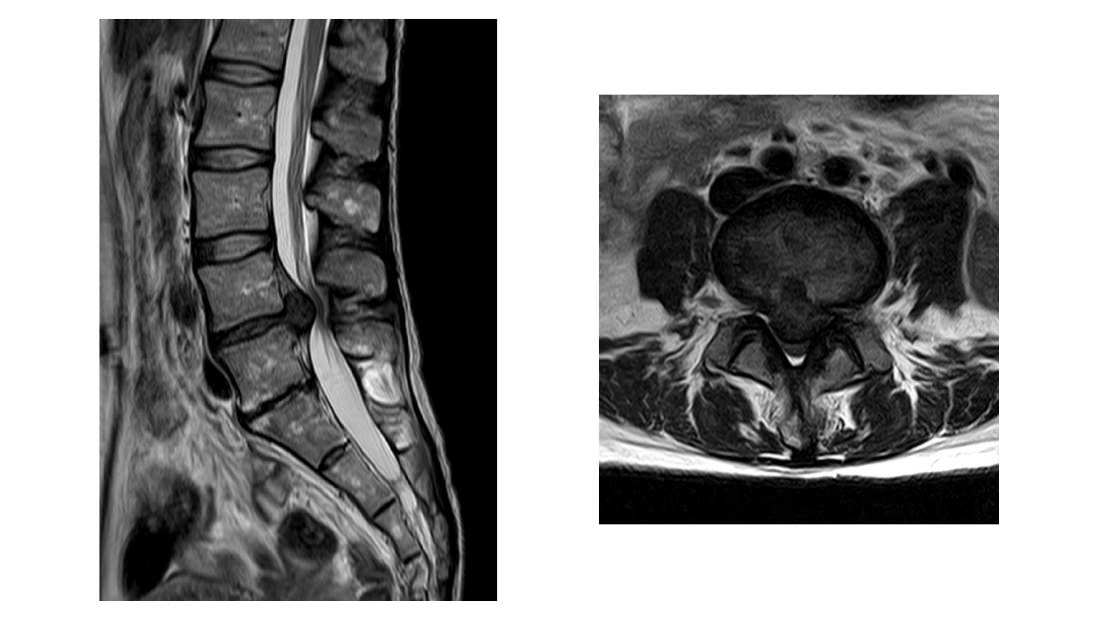

腰部脊柱管狭窄症

加齢とともに腰椎の椎体や椎間板に変性が生じます。そして脊柱管がその変性により狭くなって 中を走る神経(馬尾)が圧迫された状態を脊柱管狭窄症と呼びます。

神経が圧迫されるとその神経の担当する部位に痛みやしびれが出現します。腰痛はないこともあります。 また典型的な症状である間欠跛行や膀胱直腸障害が発生します。

歩いていると下肢にしびれや痛みが出現し歩けなくなります。少ししゃがんで休むと痛みしびれは軽快し歩けるようになりますが、 また同じくらい歩くと下肢痛が出現します。これを間欠跛行(かんけつはこう)と言います。